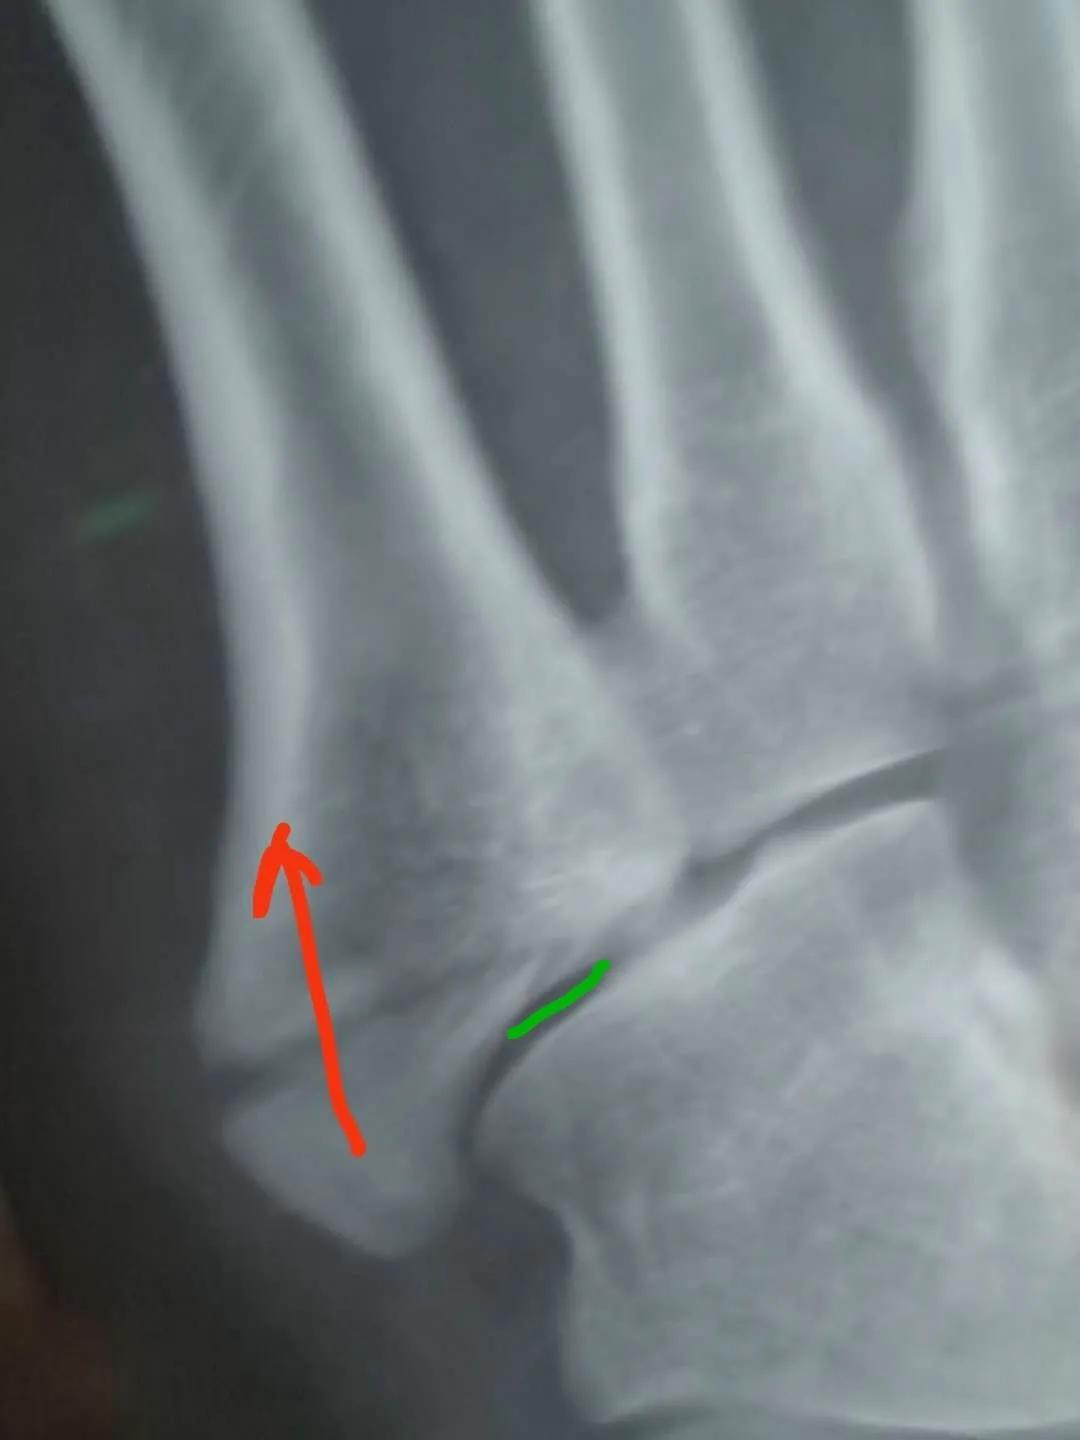

看片子骨缝比较大了,有点移位,而且中间崩碎了一块,一直找不到,后来复查才发现那个碎片掉落在骨缝当中了

此图可以看见中间碎片在骨缝里面